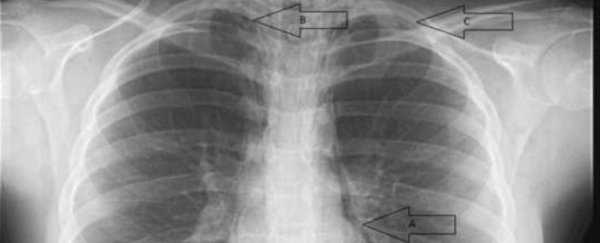

В итоге ей поставили сразу три диагноза: пневмоторакс (его еще называют спадение, или коллапс легких, скопление воздуха в плевральной полости), пневмомедиастинум (воздух в клетчатке средостения) и скопление воздуха в заглоточном пространстве.

Медики пытались найти источник воздуха с помощью компьютерной томографии, но не заметили разрывов дыхательных путей.